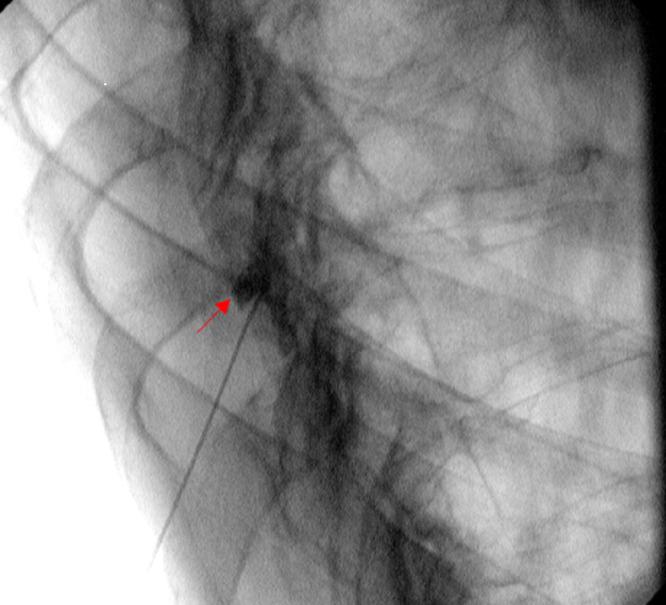

The Role of Interventional Pain Management in Proteus Syndrome: A Case Report.

Cureus. 2022 May 1;14(5):e24651. doi: 10.7759/cureus.24651. eCollection 2022 May.